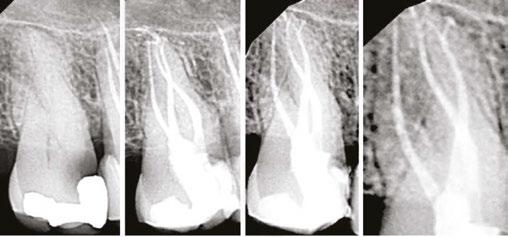

Judy McIntyre, DMD, MS Figure 1: Acutely curved and calcified buccal canal right under upper left premolar crown margin; valuable information for access and management. No. 9 also has a PARL, which was only incidentally captured Figure 2: Large PARL with destruction of the maxillary sinus floor and sinusitis as a result

About 10 years after completing residency, I opened my own practice and invested in a DEXIS CBCT. Initially, I only used it for apicoectomies and retreatments. In time, I began to realize how helpful it was for all my cases. With the 3D-scan information (Figure 1), I could have saved myself some humbling experiences and surprises. Endodontists hate surprises, and we really hate failures! Once I started using my CBCT more frequently, I was able to appreciate things that would have otherwise been intra-op surprises and plan for them prior to starting the procedure. The 3D data allows me to properly assess prognosis, determine the best course of treatment, and plan that treatment with a level of precision that is impossible otherwise.

Figure 3: Second maxillary molar with external root resorption (ERR) with incidentally captured ERR on the lower mandibular first molar as well. When there is one tooth with resorption, be suspicious of other teeth with resorption, especially on younger patients Figure 6: No PARL on PA film. Clear PARL on scan taken with medicament Figures 4 and 5: 4. Mandibular molar with a J-shaped lesion due to endo — not a vertical root fracture. Path of least resistance happens to be through a distal perio pocket, but this is an endo-perio lesion and not a VRF. Incidentally, a mucous retention cyst was captured in the sinus. 5. Healing after bridge removal and retreatment

Figure 7: Planned-for access with the scan info on this extremely calcified canine Figures 8 and 9: 8. Deep distal split with PARL. 9. Missed buccal canal; history of previous RCT, post, crown and apico Figure 10: Retreatment consultation. PA from GD Figure 11: Scan images show a previously existing strip perforation

I’m also changing my treatment plans based on the data from my CBCT. Sometimes I look at a root canal treated PA and presume I know what I will do: a retreatment or an apico. Another recent, poignant case: a lower incisor with a previous RCT and a previous apico (Figure 9). Usually, once a tooth has had an apico, there may not be much left to offer and most of the time, the default is another apico, especially as there was very little room for an implant on the lower anteriors. I scanned the tooth and saw that a whole canal had been missed — twice! The RCT and the apico had left the buccal canal completely untouched. I changed my treatment plan based on this information!